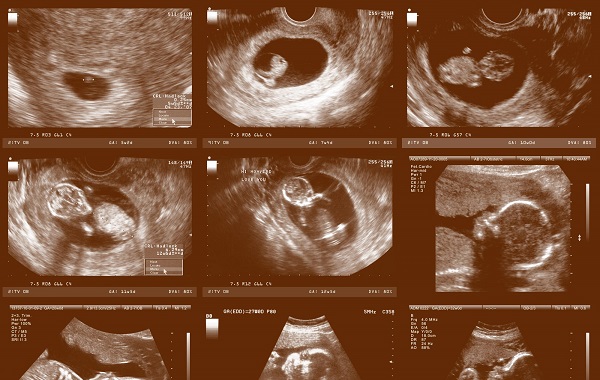

Bạn cần siêu âm thai trong thai kỳ vì nhiều lý do như kiểm tra sự phát triển, vị trí, sức khỏe và giới tính của thai nhi. Mặc dù công nghệ siêu âm an toàn cho cả mẹ và nhai nhi, nhưng các bác sĩ không khuyến nghị siêu âm thai mà không có lý do hoặc lợi ích y tế.

Siêu âm thai rất quan trọng trong quá trình mang thai

Trong ba tháng đầu thai kỳ (tuần 1 đến 12), thực hiện siêu âm thai để:

- Xác nhận có mang thai;

- Kiểm tra nhịp tim của thai nhi;

- Xác định tuổi thai;

- Dự tính ngày sinh;

- Kiểm tra đa thai (có nhiều hơn một thai nhi);

- Kiểm tra nhau thai, buồng trứng, cổ tử cung và tử cung;

- Chẩn đoán thai ngoài tử cung (thai không nằm trong buồng tử cung) ;

- Phát hiện bất thường ở thai nhi;

- Chẩn đoán nguy cơ sẩy thai.